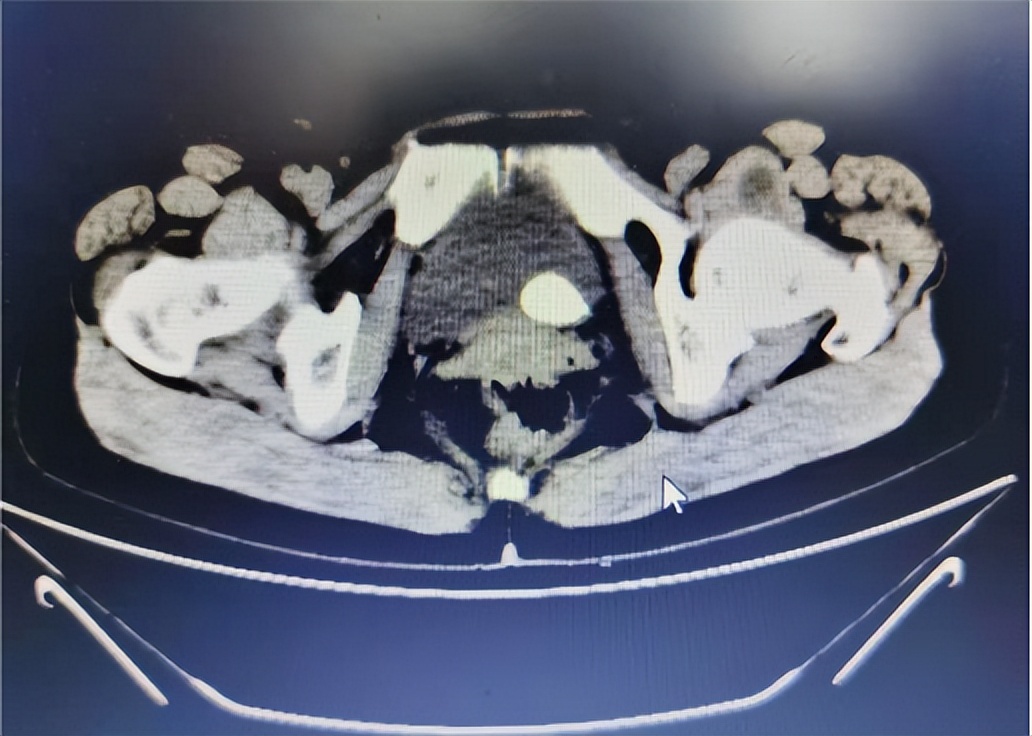

根据王阿姨的描述,我首先怀疑是尿路结石。于是,给王阿姨做了常规腹部检查,结果发现,双侧肾区未见明显异常的包块与隆起,左侧肾区叩击痛明显。随后的门诊CT结果显示,左侧输尿管结石,左侧肾盂积水并感染。看到CT结果后,我以输尿管结石收住入院。

安排王阿姨住院后,对其进行了全面的检查,检查发现患者左肾筋膜增厚,双肾见多发小囊状密度减低影,最大直径约13mm,左侧肾中极水平背阔肌内见梭形脂肪密度影,密度欠均匀,左侧髂腰肌见斑片状密度减低影,主动脉及双侧髂动脉见点状高密度影。提示患者还除左侧输尿管膀胱入口处有结石,左肾积水合并感染外,还存在双肾囊肿、左侧腰背中部背阔肌脂肪癌、腰椎退行性改变,主动脉及双侧络动脉硬化。

对王阿姨的情况进行评估后,决定先解决患者的结石情况。因此,在完善术前检查和征得患者同意后,与入院第四天行输尿管镜下激光碎石D-J管内置引流术治疗。术前从CT片观察,考虑有部分结石位于输尿管,另外一部分位于膀胱内,但是手术中发现结石全部是位于输尿管内的,结石比较大直径达到2.5cm,属于比较少见的输尿管结石。这可能是结石长期处于输尿管壁段,逐渐增大,造成了输尿管末端扩张凸向膀胱而引起的。